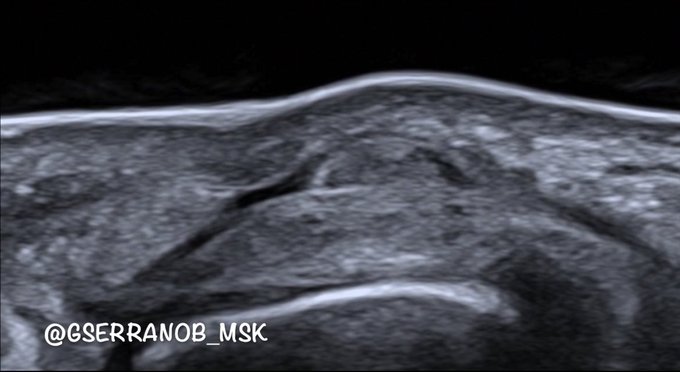

But not very often can we identify the margins of the gap. That's because when we do fist maneuvers, everything tenses up, making the gap challenging to visualize.

With a passive digital mobilization on a relaxed tendon, we can perfectly see the gap.